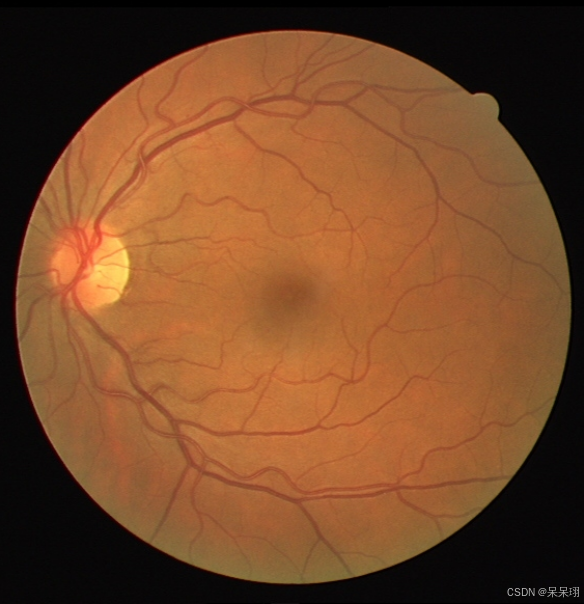

const char* img_path = "/home/ubuntu/ncnn_test/img/01_test.tif";

const char* roi_mask_path = "/home/ubuntu/ncnn_test/img/01_test_mask.png";

}4.完整代码和推理结果